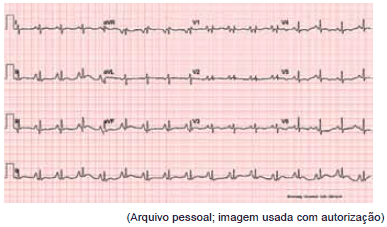

O seguinte eletrocardiograma de um menino de nove meses é compatível com qual cardiopatia congênita?

Paciente foi transferido de urgência em vaga zero de UBS para pronto-socorro cardiológico sem história de cardiopatia congênita prévia. Mãe refere que nasceu sem intercorrências, de parto normal, e teve alta no segundo dia de vida. Notou que sua criança tinha dificuldades às mamadas e ficava roxo aos esforços. Após exame físico e cuidados imediatos de intubação orotraqueal, cateter venoso central e sonda nasogástrica, foram feitos os seguintes exames:

Qual é o diagnóstico mais provável?